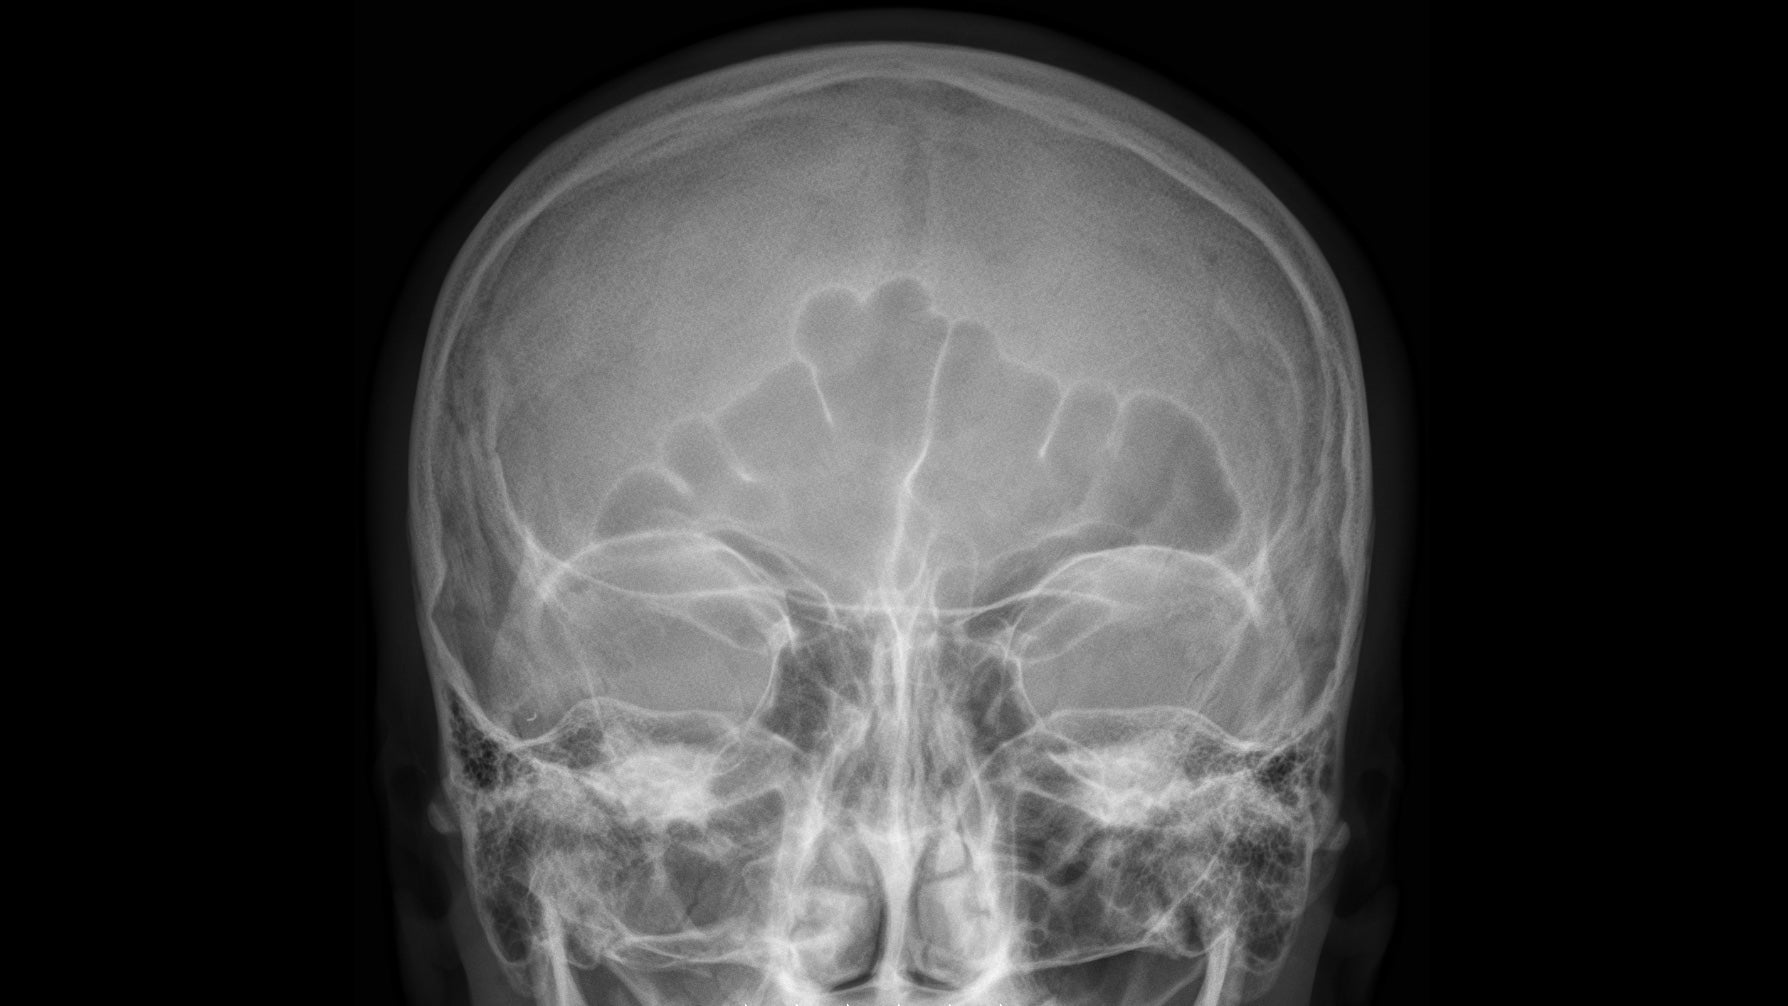

Esta zona se describe en medicina como el “triángulo de peligro o de la muerte”, y está formada por tres vértices que se encuentran en el entrecejo y las comisuras de la boca, lugar donde tenemos una gran cantidad de vasos sanguíneos que se comunican con la parte posterior de la cabeza.

Voigt recalca que tan solo en el peor de los escenarios se puede producir un tipo de infección en este área que puede ser muy peligrosa. La razón: las mismas venas que sacan la sangre de la nariz se encuentran con las venas que también sacan la sangre del cerebro.

Si esos gérmenes llegan hasta allí, explica Voigt, podrían provocar enfermedades como la meningitis (donde las membranas protectoras de la médula espinal y el cerebro se inflaman), o un absceso cerebral (un tipo de inflamación e hinchazón que ocurre en el cerebro, relacionado con una infección).